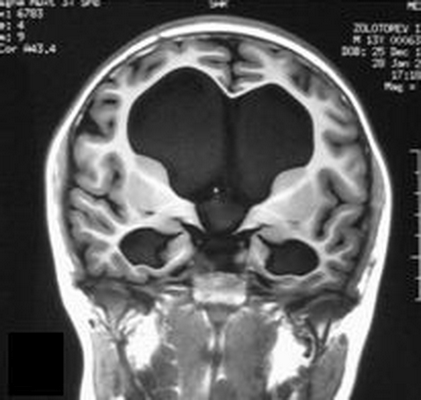

При магнитно-резонансной томографии получают послойные снимки исследуемой анатомической области. При изучении сканов врач видит мозговое вещество и выявляет отклонения от нормы. МРТ отчетливо показывает гидроцефалию. Метод информативен на ранних этапах развития заболевания, даже при отсутствии у пациента характерных симптомов. Детализация снимков позволяет врачам выявить водянку головного мозга, определить тип, диагностировать сопутствующие заболевания.

Водянка головного мозга при МР-сканировании в коронарной проекции

Признаки гидроцефалии у взрослых по МРТ

Проявления патологии на снимках бывают прямыми и косвенными. Первые связаны с расширением желудочков мозга (III, IV и боковых (в начальном периоде — в области передних рогов и тела)), водопровода и/или субарахноидального пространства (конвекситально, в области базальных цистерн, Сильвиевых борозд и пр.). Косвенные признаки на МР-сканах:

- межжелудочковый индекс свыше 0,5;

- перивентрикулярный отек при напряженной водянке;

- смещение гипоталамуса вниз;

- локальное выпячивание крыши боковых желудочков и др.

Дополнительно на томограммах определяют причину водянки головного мозга — основное заболевание.

Признаки гидроцефалии головного мозга на МРТ

Признаки гидроцефалии на снимках МРТ бывают прямыми и косвенными. Первые связаны с расширением желудочков мозга (III, IV и боковых (в начальном периоде — в области передних рогов и тела)), водопровода и/или субарахноидального пространства (конвекситально, в области базальных цистерн, Сильвиевых борозд).